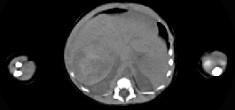

男,5天,上腹部膨隆,CT所见如图,最可能的诊断是()A.原发性肝癌B.肝母细胞瘤C.肝血管瘤D.肝脓肿E.肝转移瘤

问题 男,5天,上腹部膨隆,CT所见如图,最可能的诊断是()

选项 A.原发性肝癌 B.肝母细胞瘤 C.肝血管瘤 D.肝脓肿 E.肝转移瘤

答案 B